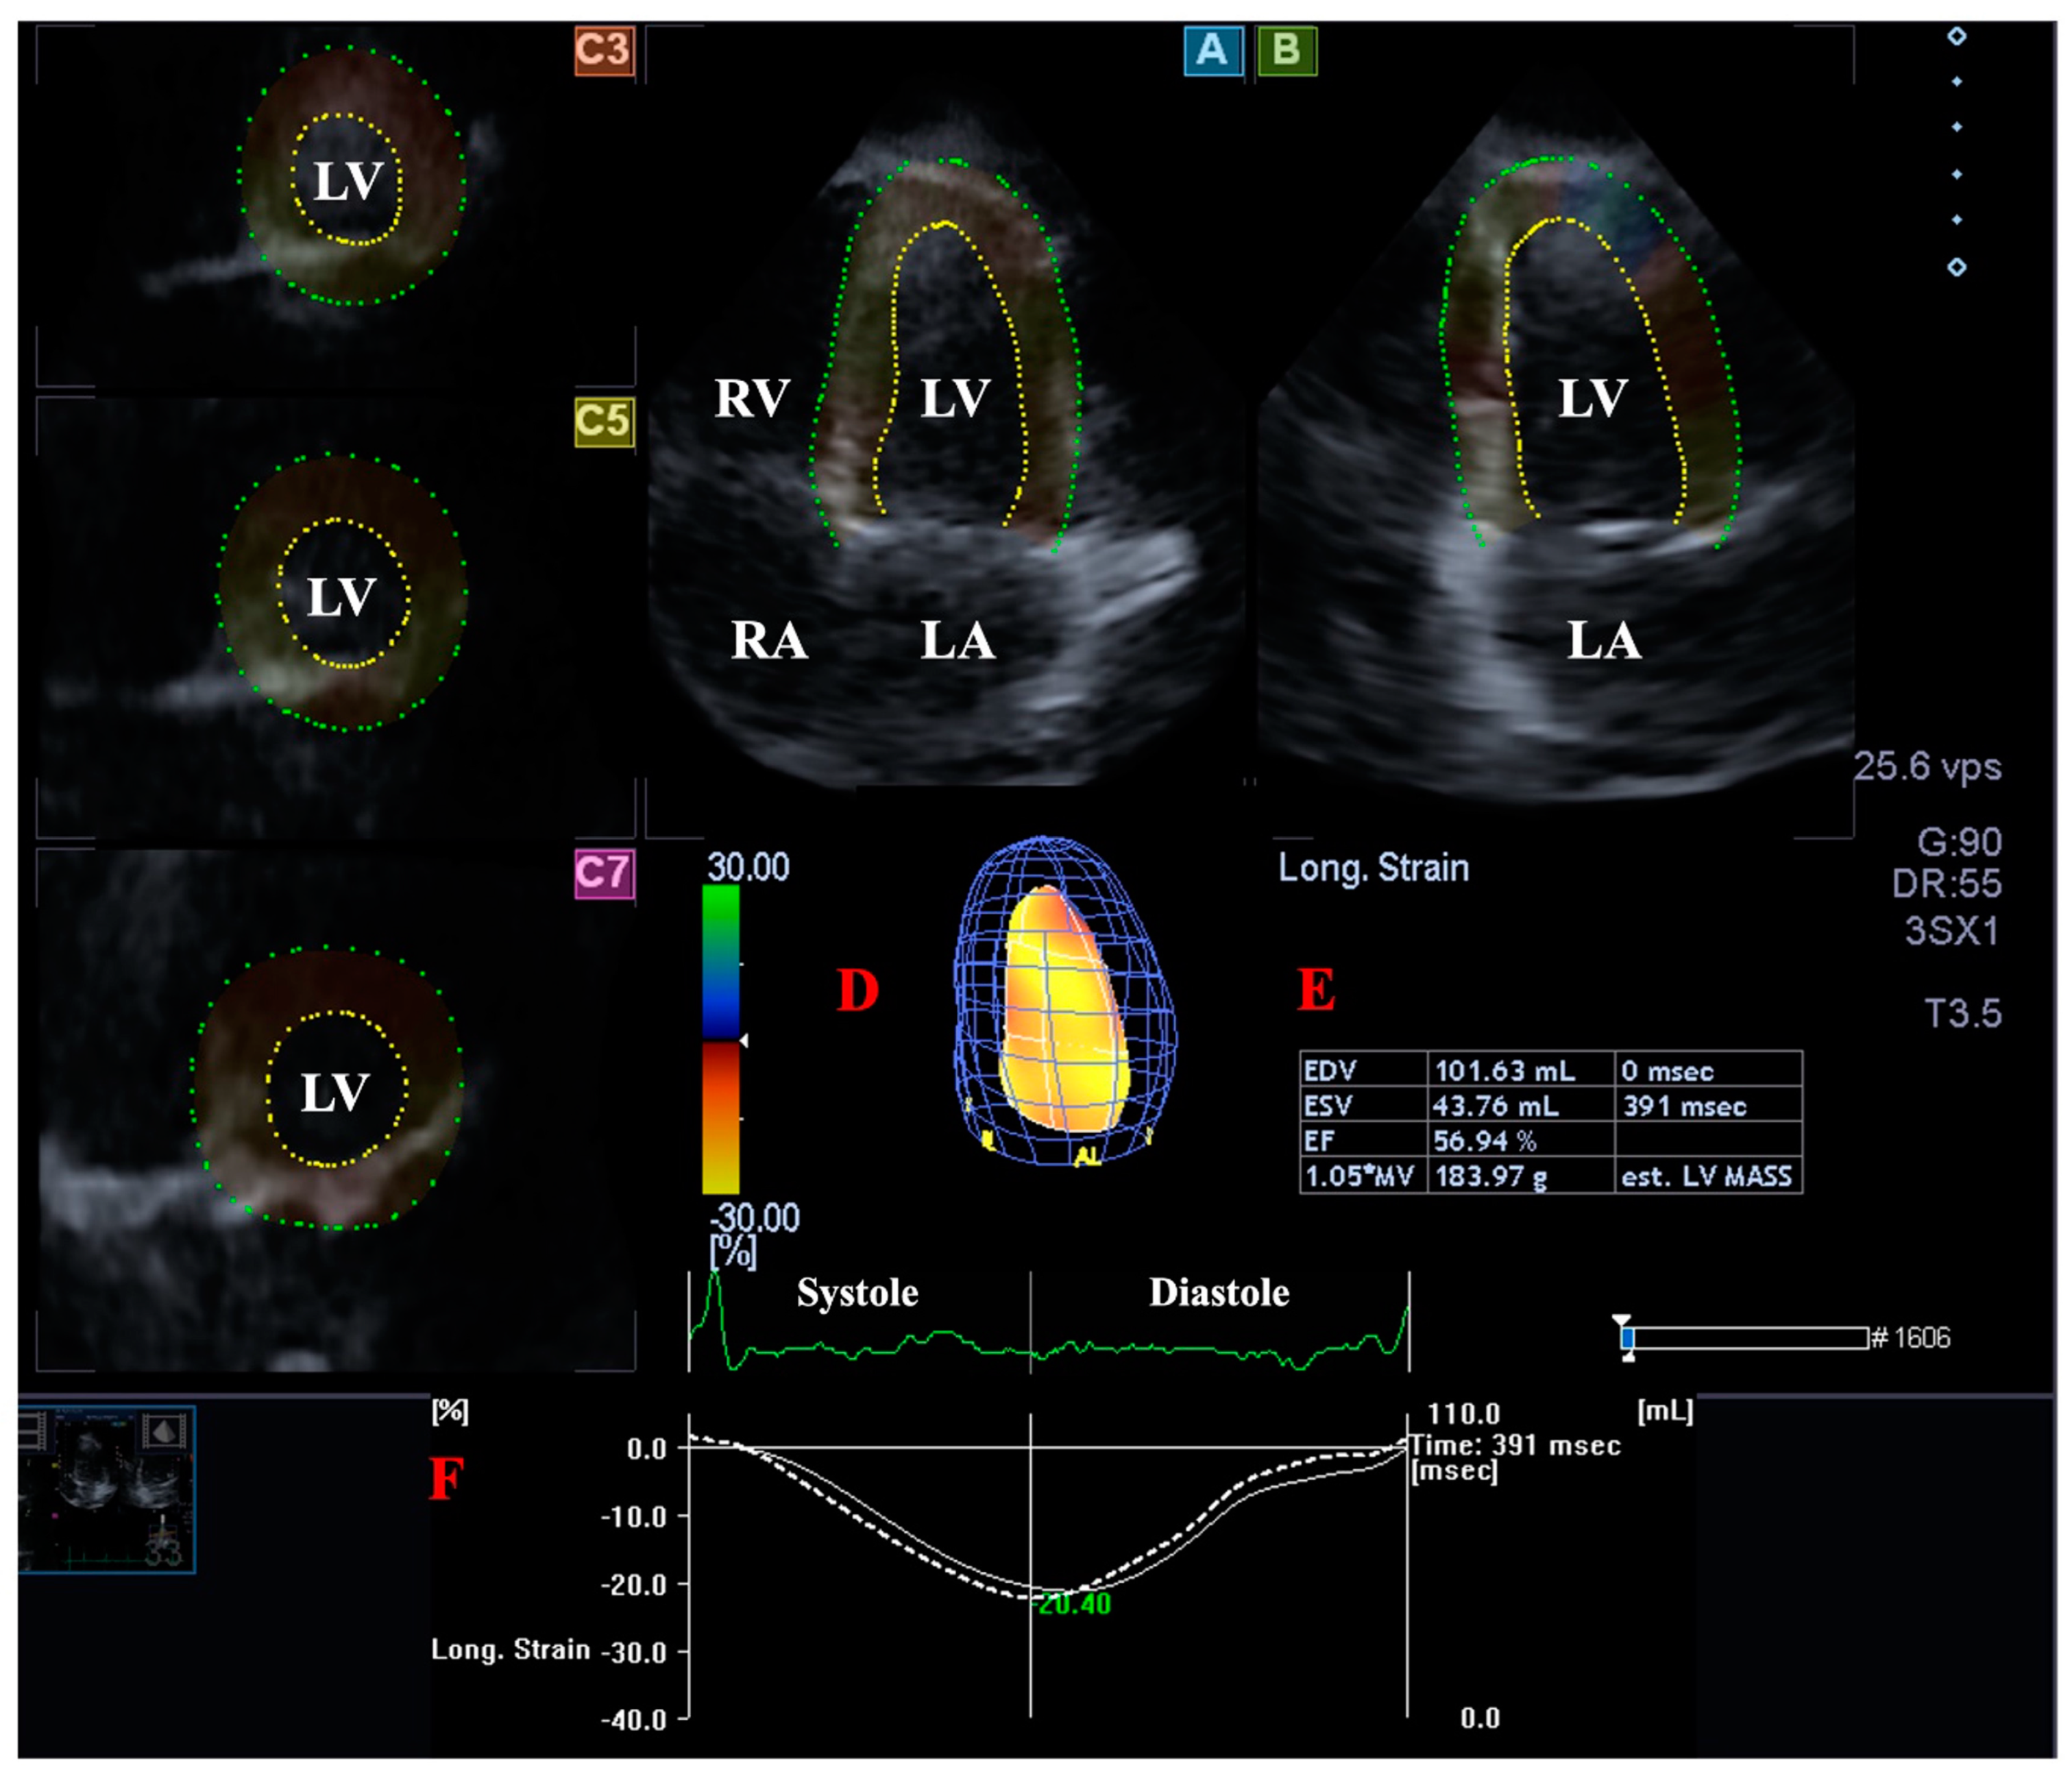

2.4. LV Volume Measurement with 3DSTE

2.5. LA Volume Measurement with 3DSTE